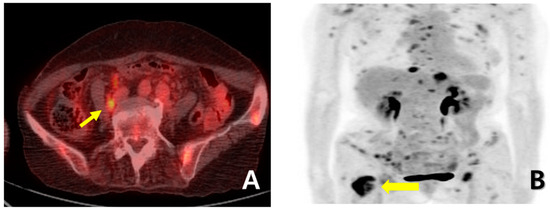

A 72-year-old female woman visited the outpatient clinic for rectal high-grade dysplasia detected during a screening test. She had a history of total thyroidectomy for thyroid cancer 25 years ago. She was admitted for endoscopic submucosal dissection for rectal cancer, and a mass in the right breast was observed during physical examination at admission. She received endoscopic submucosal dissection for rectal cancer, and ultrasonography-guided breast gun biopsy was performed during admission. On pathologic examination of the patient’s rectal cancer, the size of the tumor was 1 cm, and it was a moderately differentiated adenocarcinoma with mucosal invasion. She no longer received additional treatment for rectal cancer. During an ultrasonography examination of the right breast, a 4.9 × 4.4 × 2.2 cm irregular spiculated heterogenous echoic mass was observed. Pathologic examination revealed invasive ductal carcinoma, nuclear grade 2/3, and metastatic ductal carcinoma in the right axillary lymph node. Neoadjuvant chemotherapy, which was combined with Adriamycin, cyclophosphamide, and docetaxel, was performed. After four cycles of neoadjuvant chemotherapy, partial remission was observed. She underwent right modified radical mastectomy (MRM). Postoperative pathological examination revealed invasive ductal carcinoma, and pathologic stage ypT3(8 × 7 × 2.3 cm)ypN3(22/29). Immunohistochemical staining for estrogen receptor (ER), progesterone receptor (PR), and human growth factor receptor 2 (HER-2) were all negative (Figure 1A). After surgery, adjuvant chemotherapy based on capecitabine was performed along with radiation therapy. Nine months after MRM, gastroscopy was performed because of epigastric pain and discomfort. A gastroscopy revealed a 1 cm sized elevated mass in the posterior wall of the fundus, and endoscopic biopsy was performed (Figure 1B). Microscopic examination of the biopsy specimen showed solid nests or cords of tumor cells with histologic features resembling poorly differentiated carcinoma at initial diagnosis (Figure 1C). Immunohistochemical staining for GATA3 (GATA binding protein 3) and gross cystic disease fluid protein-15 (GCDFP-15) was carried out to rule out the possibility of metastatic breast cancer. Since both markers were negative in both breast cancer and in gastric cancer, it was inconclusive for determining the origin of the gastric tumor (Figure 2A–D). Moreover, the small size of the biopsy specimen itself brings limitations in evaluating the histologic features of entire gastric tumor. Therefore, a resection of the entire mass was needed. As the tumor cells were poorly differentiated, gastrectomy was considered more than endoscopic resection. Preoperative examination, including abdomen-pelvis CT and chest CT, was performed to check for distant metastasis, and no evidence of distant metastasis was found. She underwent totally laparoscopic total gastrectomy 10 months after MRM. The patient was diagnosed with T1bN1M0 gastric cancer according to AJCC 8th edition. Gross examination of the resected specimen revealed a well-demarcated mass measuring 1 × 0.7 cm. The entire mass was microscopically examined, and a poorly differentiated carcinoma that invaded the submucosa was identified; however, it differed from the general histological features of primary gastric adenocarcinoma for the following reasons: (1) No surface epithelial cells showed dysplasia or malignant change. (2) All tumor cells were located in the lamina propria with a solid nest or cord patterns with no glandular growth pattern (Figure 3A). Therefore, the tumor was more likely to be metastatic breast cancer than primary gastric cancer. It was reviewed again with the pathological findings of previous BC, and the histologic features of breast cancer and gastric cancer were almost identical. Additionally, cytokeratin CK 7 (CK7) immunostaining showed diffuse and strong positivity in both the gastric and breast specimens (Figure 3B,C). As a result, possible gastric metastasis of BC was diagnosed because the histological shape and immunohistochemical staining findings were consistent with BC. After the totally laparoscopic total gastrectomy, the patient received palliative first-line chemotherapy with paclitaxel and cisplatin (CDDP). Two months after gastrectomy, she was diagnosed with para-aortic lymph node metastasis and multiple bone metastases (Figure 4A,B). She underwent hip arthroplasty due to pathologic fracture of the right hip joint three months after gastrectomy, and she expired six months after gastrectomy.

Figure 3. (A) The gastrectomy specimen showed tumor cells with histopathologic features identical to those of carcinoma of the breast, which invaded the submucosa of the stomach (×40). The cytokeratin 7 immunostaining showed diffuse and strong positivity in both gastric cancer (B) and breast cancer (C).